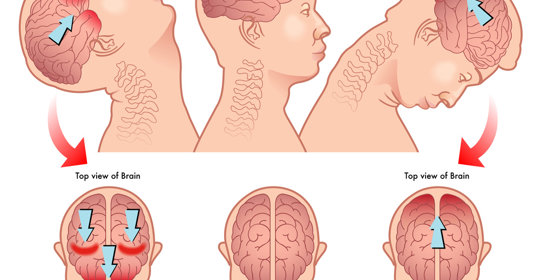

嬰兒囟門:頭痛、噁心、前囟膨脹

前臂旋轉痛:不同病症導致的頭痛與手部不適